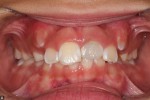

This is a 9yo girl with a high esthetic desire (wants to be a model/actor). She avulsed tooth #9 about 3 years ago, and she has been under treatment with other endodontists. I guess they attempted revascularization with MTA about year ago. #9 is ankylotic with a few mm’s infraposition. It is gray due to the MTA. #8 is slightly yellow/white due to calcification/obliteration but she says she feels cold testing and it is otherwise asymptomatic.